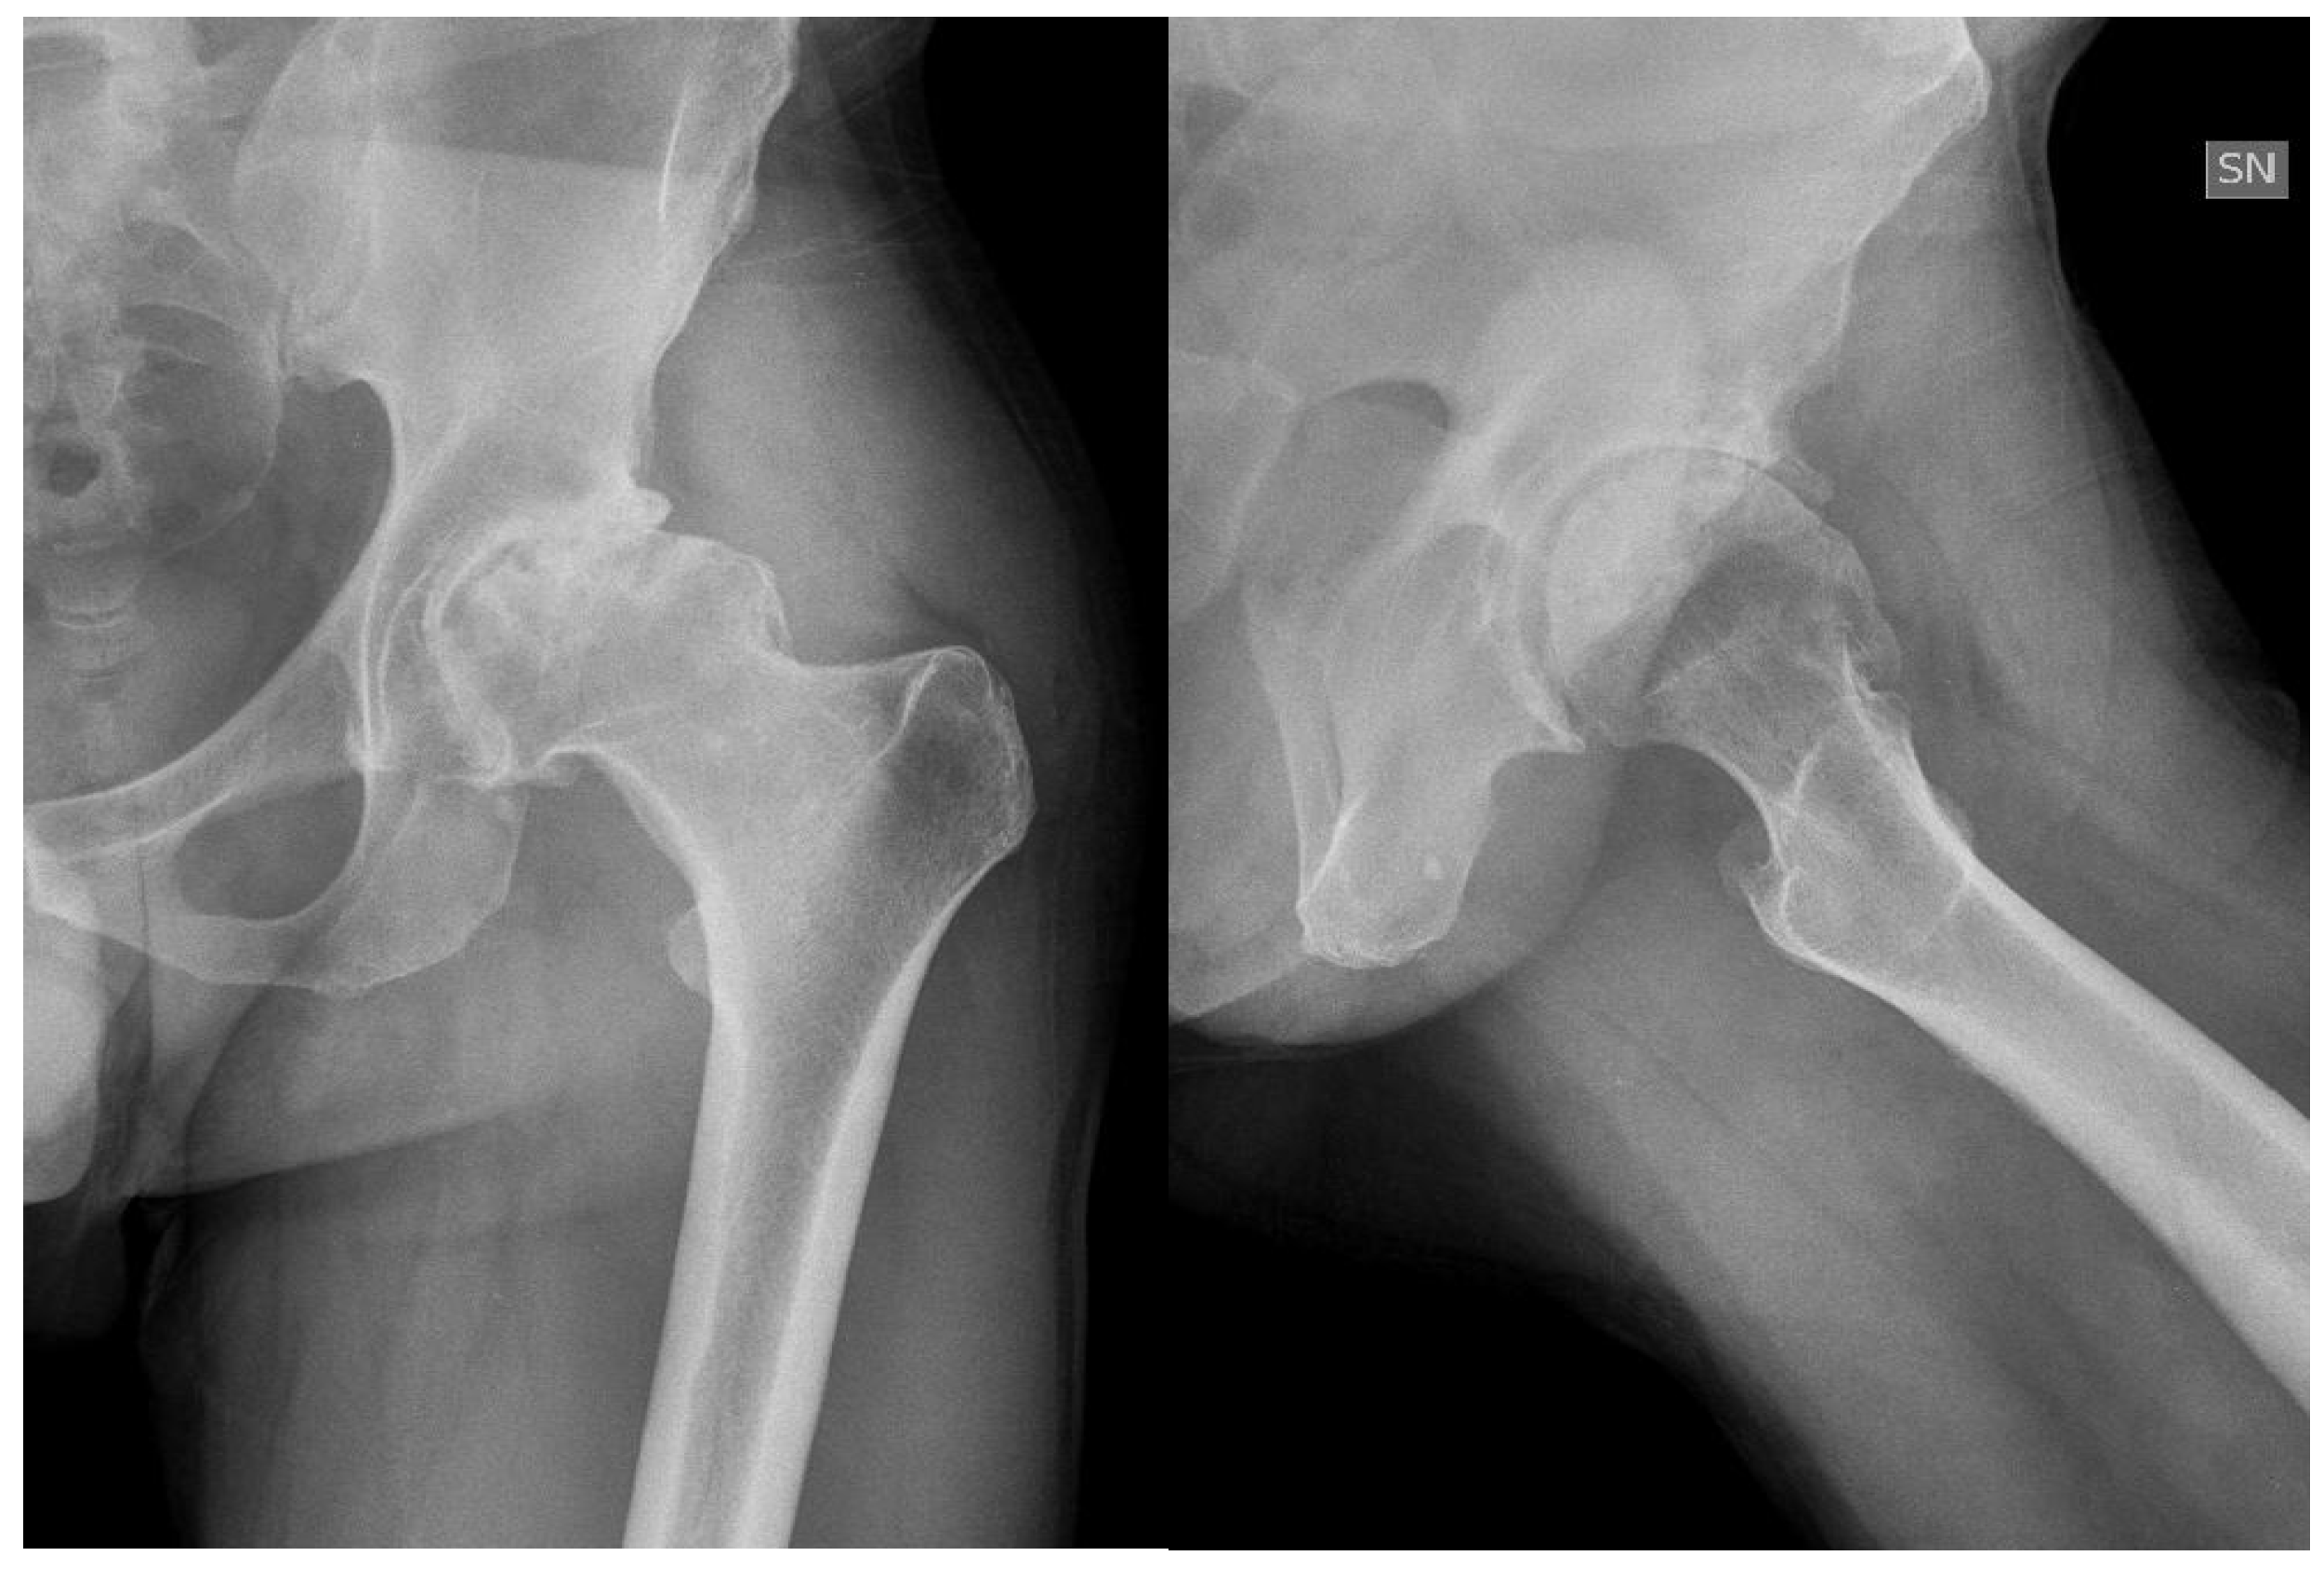

The modern management of haemophilia is usually deemed to be sufficient to prevent any form of hip arthropathy, except in the case of inhibitors. However, patients with recurrent bleeding, with a history of trauma or with associated femoroacetabular impingement are prone to develop haemophilic arthropathy (Figure 1).

Figure 1. Forty-six-year-old haemophilic subject affected by severe haemophilia A, with inhibitors, with symptomatic left hip arthropathy secondary to femoral acetabular impingement.